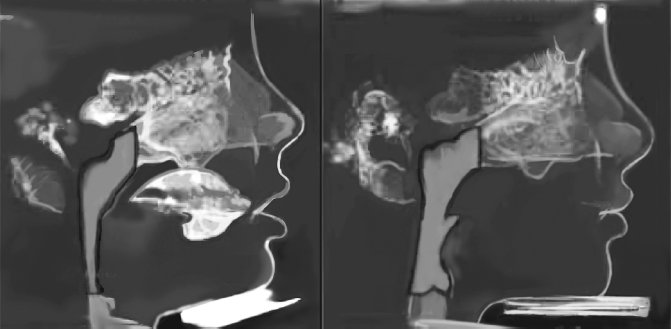

Рисунок 6. Результаты лечения, проведенного ортодонтом Джоном Мью (фотографии любезно предоставлены Джоном Мью)

Рисунок 7. Расширение дыхательных путей у мальчика после ортотропического лечения и исправления осанки лица. Подобный эффект продемонстрирован на шестом рисунке

Рисунок 8. Девочке слева сказали, что для исправления ее опущенного подбородка необходима операция. Ортотропическое лечение с помощью системы Biobloc и упражнений по исправлению осанки лица привели к поразительным результатам, которые можно увидеть на правой фотографии. Ни ортодонтия, ни ортопедия не могут гордиться такими впечатляющими изменениями челюсти (Фотографии любезно предоставлены Джоном Мью)

Рисунок 9. При правильной осанке лица и выступающей вперед челюсти губы становятся более полными (изменения, произошедшие за 12 месяцев)